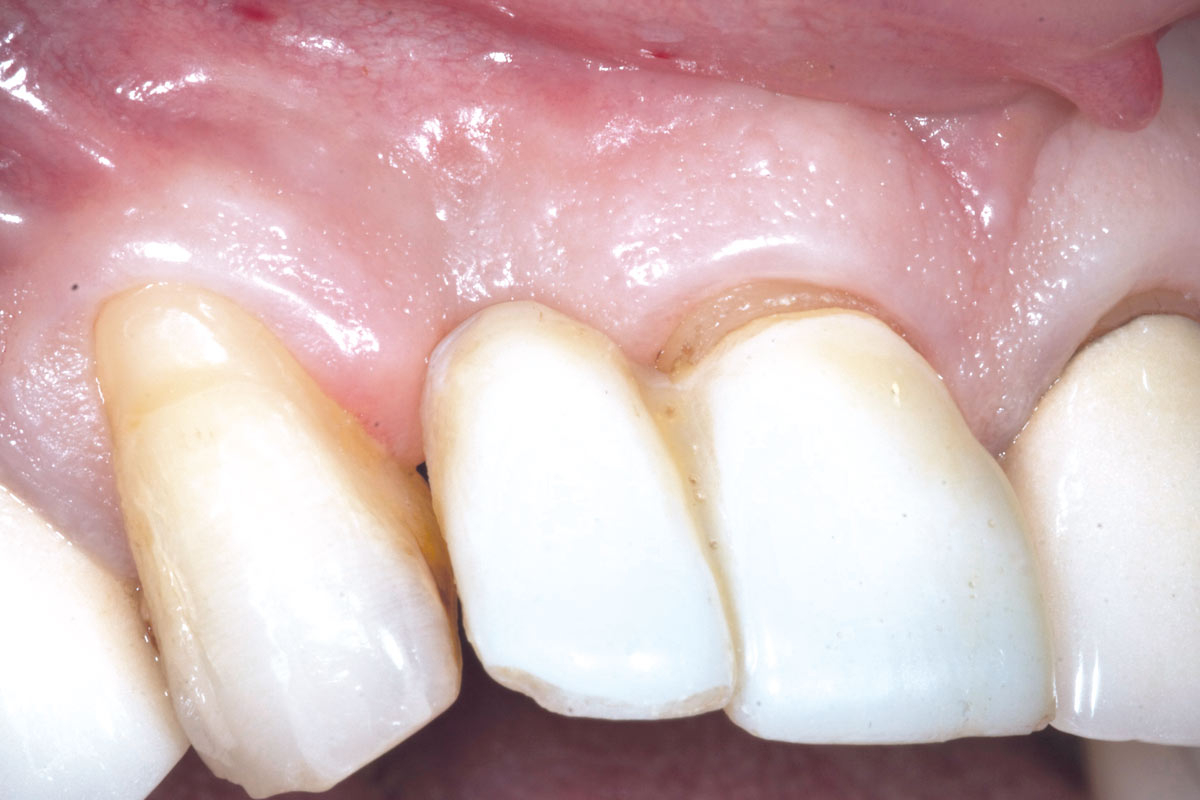

1/19 - Initial situation: Inflammated tooth #12Bone augementation with maxresorb® - Dr. R. Cutts